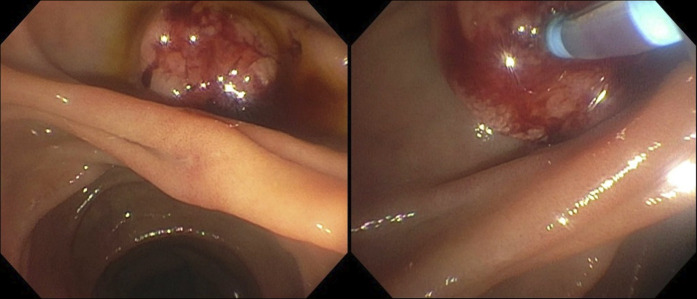

胆道射频消融是一种新兴的辅助和姑息性治疗壶腹和胆道肿瘤的患者。鉴于这些恶性肿瘤的高死亡率,有关长期并发症的数据有限。我们报告一个独特的病例括约肌切开术再狭窄导致胆道梗阻,在一个98岁的妇女壶腹腺癌的历史,治疗乳头切除和胆道射频消融(RFA)。内镜逆行胆管造影显示括约肌切开术部位再狭窄,通过重复括约肌切开术和支架置入术成功处理。本病例强调括约肌切开术再狭窄是胆道RFA的潜在晚期并发症,并强调RFA后患者需要意识到延迟性胆道梗阻。

Biliary radiofrequency ablation is an emerging adjunctive and palliative therapy for patients with ampullary and biliary tumors. Given the high mortality for these malignancies, data on long-term complications are limited. We report a unique case of sphincterotomy restenosis causing biliary obstruction in a 98-year-old woman with a history of ampullary adenocarcinoma treated with papillectomy and biliary radiofrequency ablation (RFA). Endoscopic retrograde cholangiopancreatography revealed restenosis at the sphincterotomy site, managed successfully with repeat sphincterotomy and stenting. This case highlights sphincterotomy restenosis as a potential late complication of biliary RFA and emphasizes the need for awareness of delayed biliary obstruction in post-RFA patients.